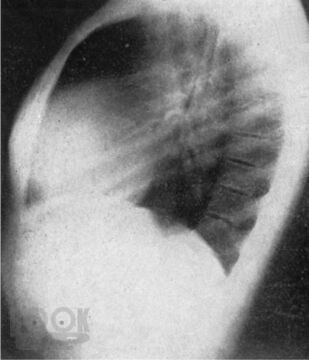

Монография всемирно известного автора посвящена вопросам клинической диагностики заболеваний сердца. Детально освещены общее исследование больного, сбор анамнеза и анализ жалоб, оценка симптомов, полученных при физикальном обследовании, а также при использовании рентгенологического и электрокардиографического методов. Для каждого заболевания автор выделяет решающие симптомы-“ключи”, помогающие установить точный диагноз.